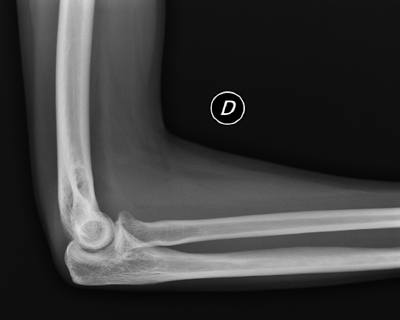

En RX simple no se aprecian claras líneas de fractura (figura 1 y figura 2), y ante la duda se decide realizar proyecciones adicionales para intentar despejar cabeza de radio. Se realizan dos proyecciones adicionales: oblicua de codo (oblicuando todo el cuerpo del paciente, para no movilizar el codo por dolor), y perfil de codo angulado el tubo caudalmente entre 10-15 grados. En ambas proyecciones se visualiza una clara fractura del mismo (figura 3 y figura 4).

(figura 3)